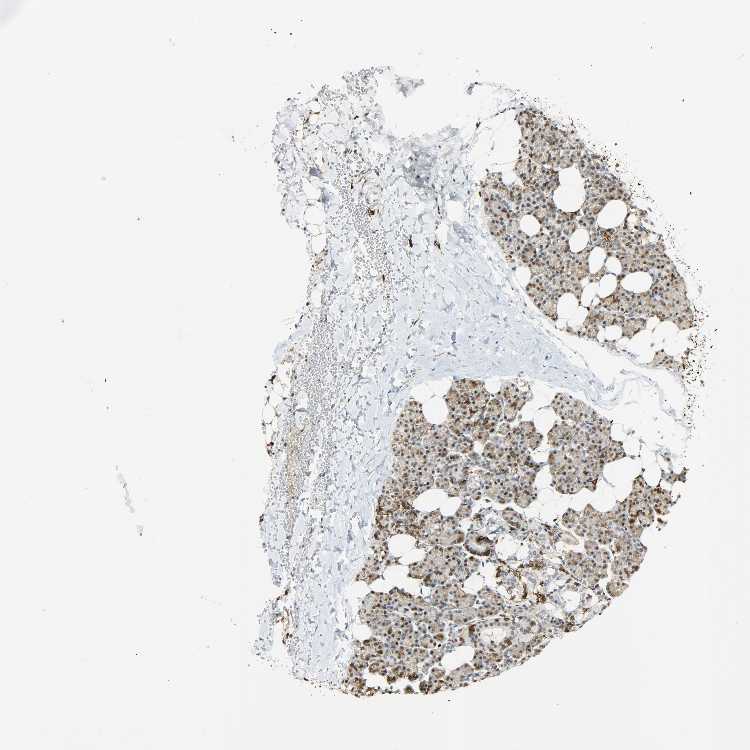

SALIVARY GLAND - Antibody stainingi

Antibody staining in the annotated cell types in the current human tissue is reported as not detected, low, medium, or high, based on conventional immunohistochemistry profiling in selected tissues. This score is based on the combination of the staining intensity and fraction of stained cells.

Each image is clickable and will lead to virtual microscopy that enables deeper exploration of all samples and also displays staining intensity scores, fraction scores and subcellular localization as well as patient and tissue information for each sample.

Antibody HPA004765Antibody CAB000143Antibody CAB001995

Glandular cells LowNot detectedLow